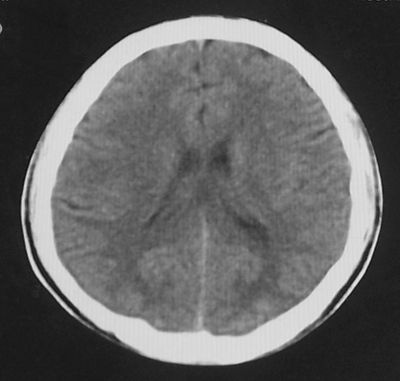

患者、男、18y,头痛5天入院。

左小脑、右丘脑区低密度影,无明显强化及占位表现,男18y,先考虑脑部炎性病变,如脑炎、血行播散性感染等,建议结合临床如脑脊液检验。

单独看左侧小脑半球的不规则形囊性低密度灶,从发病部位、年龄以及无强化、无占位效应的特点可以考虑毛细胞瘤型星形细胞瘤。同样,如果单独看右侧丘脑的近圆形低密度,也可以考虑囊变形星形细胞瘤。只是胶质细胞瘤一般为单发直接浸润、蔓延生长,而不是在脑内同时出现多个病灶,且瘤周没有一点儿水肿,暂时不予以考虑。

脑炎倒是首先可以考虑,只是临床症状、病史不很符合,建议狼兄仔细了解病史以及其他临床资料。

同时,现在已经进入冬天,一氧化碳中毒也需要考虑进去。不知道增强是什么时间做的,与平扫间隔几天?如果中间时间比较久而且进行吸氧等治疗,则平扫所示右侧颞叶密度比较低、右侧小脑半球以及脑桥也似有片囊状低密度,但在增强却没有发现就可以比较合理的解释了。